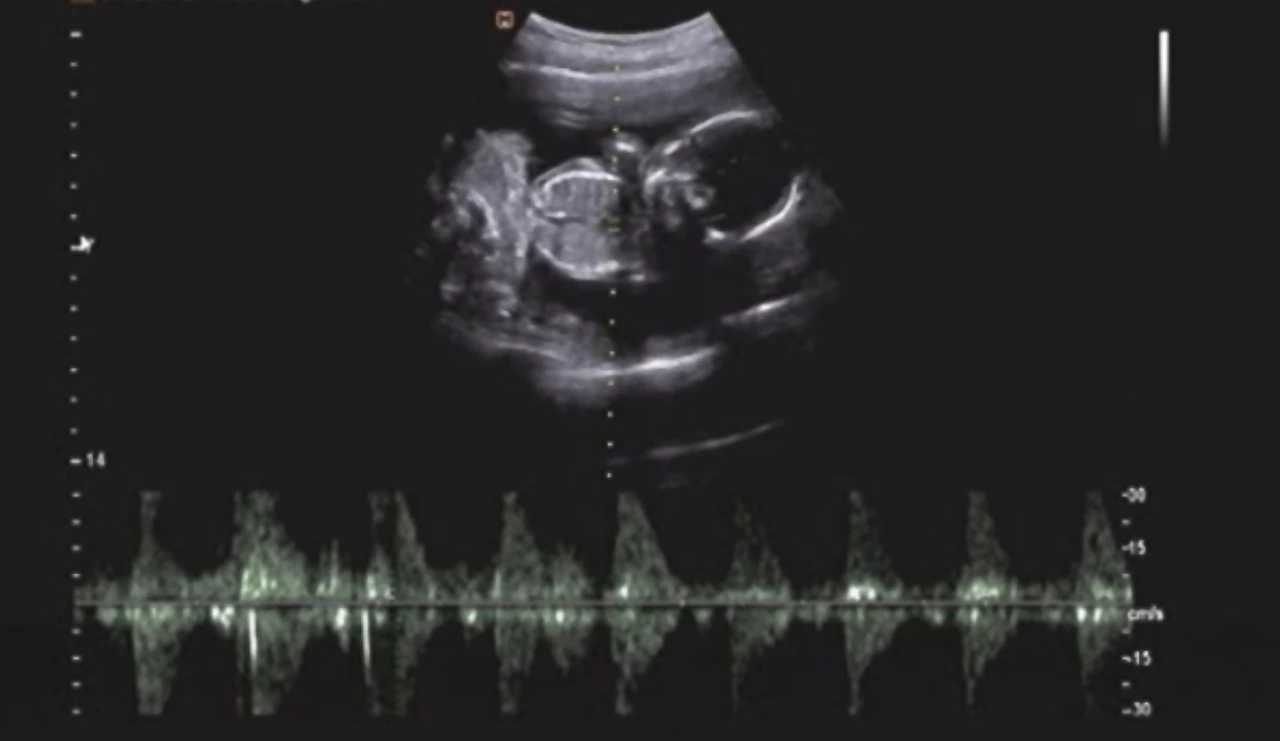

이게 무슨 개소리인가 싶지만 어쩔 수 없다. 아직 나도 제대로 모르는 내 마음을 조리 있게 설명하기란 불가능하니까. 지난 상담 때 이런 얘기를 두서없이 뱉어내는 나를 가만히 보던 상담 선생님은 과학적으로 설명되지 않는 일-엄마 뱃속에 있을 때 근원적인 상처로 인해 트라우마가 발생-을 어떻게 생각하는지 물었다.

영화 '나비효과' 감독판은 결말이 다르다는 사실을 알고 있는지. 사랑하는 여자의 행복을 위해 수없이 과거로 돌아가 인생을 고쳐나가던 주인공은, 결국 모두의 행복을 위해 자신을 희생하는 선택을 한다. 왜 갑자기 이 오래된 영화가 생각났냐 하면, 엄마에게 들었던 탄생 비화가 문득 떠올랐기 때문이다. 지금도 목을 감싸는 걸 그다지 선호하지 않지만 어렸을 때는 폴라를 못 입을 정도로 질색했었다. 그런 얘기를 하던 어느 날 엄마는, 내가 태어날 때 목에 탯줄이 감겨 있었다는 얘기를 했다.